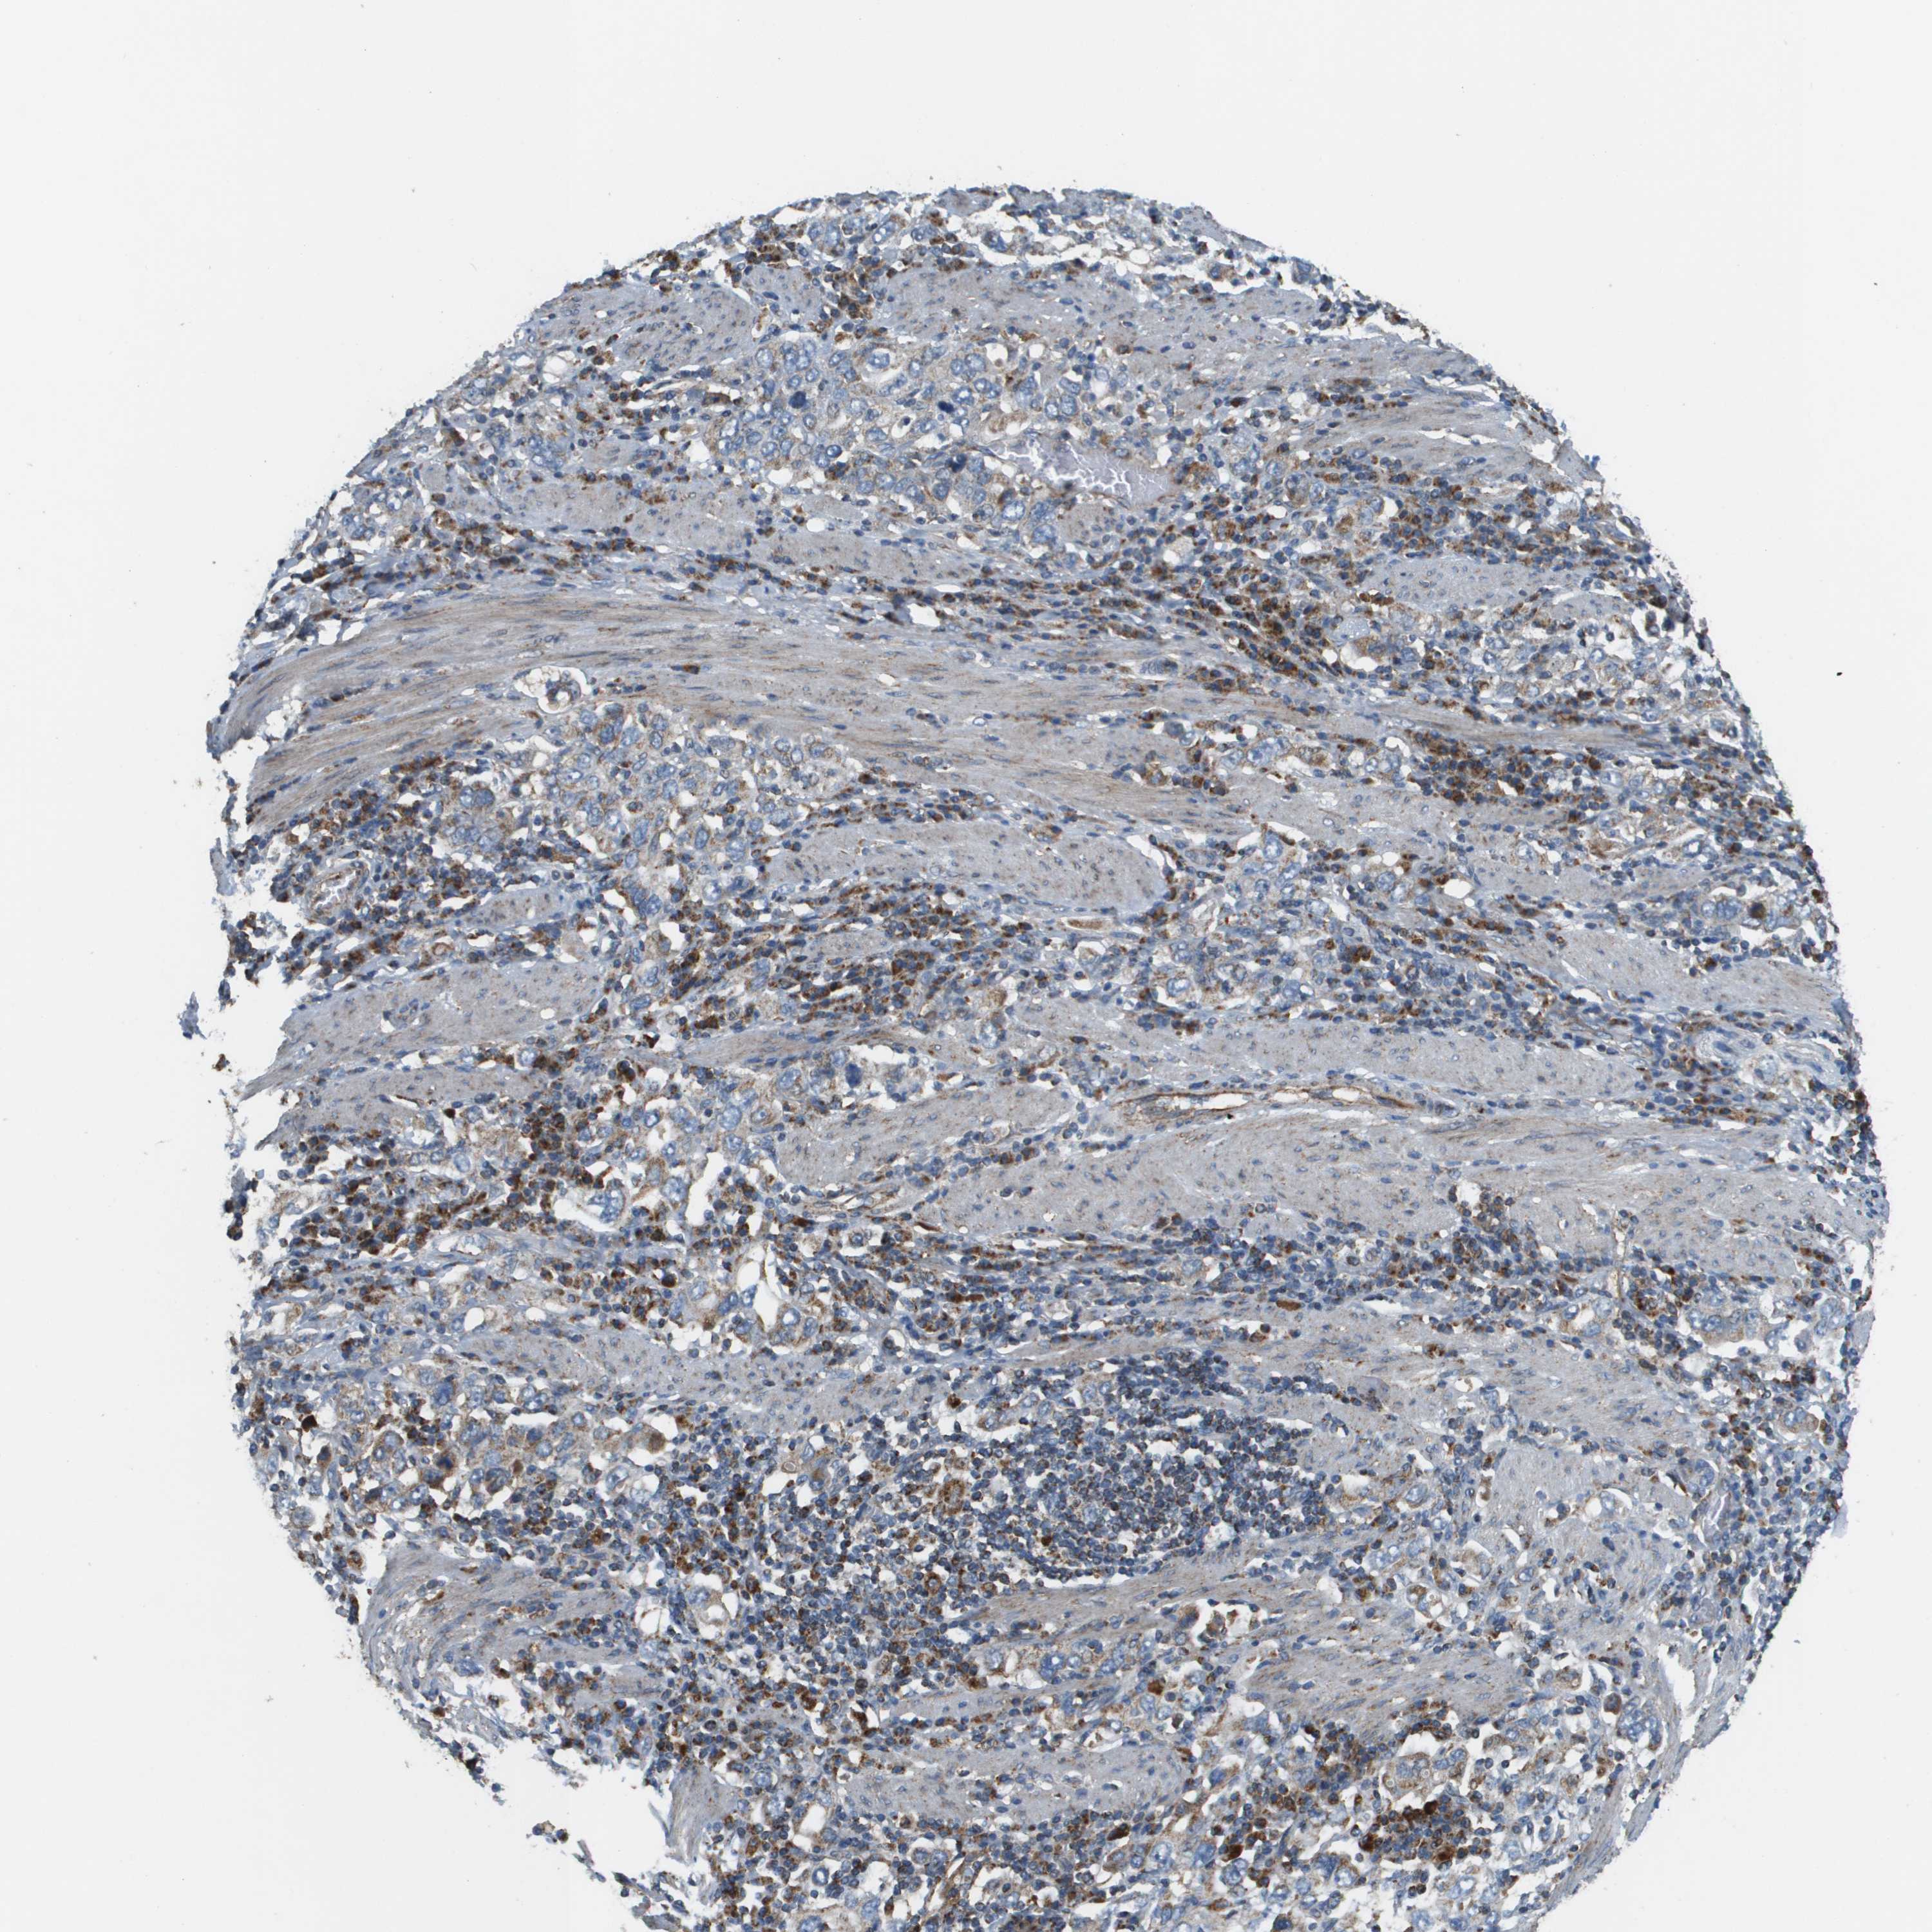

STOMACH CANCER - Protein expressioni

A mouse-over function shows sample information and annotation data. Click on an image to view it in a full screen mode. Samples can be filtered based on level of antibody staining by selecting one or several of the following categories: high, medium, low and not detected. The assay and annotation is described here.

Note that samples used for immunohistochemistry by the Human Protein Atlas do not correspond to samples in the TCGA dataset.

Antibody stainingi

Antibody staining in the annotated cell types in the current human tissue is reported as not detected, low, medium, or high, based on conventional immunohistochemistry profiling in selected tissues. This score is based on the combination of the staining intensity and fraction of stained cells.

Each image is clickable and will lead to virtual microscopy that enables deeper exploration of all samples and also displays staining intensity scores, fraction scores and subcellular localization as well as patient and tissue information for each sample.

Antibody HPA017238

Staining

High

Medium

Low

Not detected

Intensity

Strong

Moderate

Weak

Negative

Quantity

>75%

75%-25%

<25%

None

Location

Nuclear

Cytoplasmic/membranous

Cytoplasmic/membranous,nuclear

Adenocarcinoma, NOS